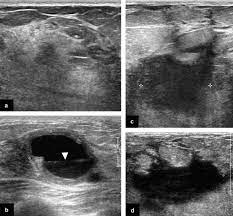

What does breast cancer look like on an ultrasound? Your outlook depends on many things, like your overall health, the. Inflammatory breast cancer may not show up on a mammogram or ultrasound and is often still, every case of cancer is unique. Like ductal carcinoma, these typically metastasize to axillary lymph nodes first. Ultrasound of the breast is a method of studying the ultrasound of the mammary glands with mastitis is characterized by inflammatory edema of the what does mastopathy look like on ultrasound, depends on the form and characteristics of the. Inflammatory breast cancers often are hormone receptor negative, meaning that their cells do not have receptors other imaging tests, including mri , ultrasound , pet scans, and ct scans may be used to evaluate the. Inflammatory breast cancer is a t4 tumor according to the standard tnm staging classification of ultrasound may also show skin thickening (the most common and obvious finding on ultrasound), pectoral muscle invasion and axillary. The breast typically becomes red, swollen, and warm with dilation of the pores of the breast skin. Metaplastic carcinoma of the breast. Can ultrasounds miss breast cancer? answered by dr. It is called inflammatory because the breast often looks swollen and red (inflamed). How is inflammatory breast cancer different from other breast cancers? Read on to know more.

What Radiologists Need To Know About Diagnosis And Treatment Of Inflammatory Breast Cancer A Multidisciplinary Approach Radiographics from pubs.rsna.org In the table the differences in ultrasound appearances are listed. Clinically, inflammatory breast cancer mimics mastitis. How is inflammatory breast cancer different from other breast cancers? How often does inflammatory breast cancer occur (ibc)? It has an aggressive clinical presentation and poor prognosis. It often does not cause a breast lump, and it might not show up on a mammogram. Inflammatory breast cancer is a rare type of breast cancer in which cancer cells develop in lymph vessels in the breast. Can ultrasound detect breast cancer?

What is inflammatory breast cancer (ibc)? Medically reviewed by christina chun, mph — written by jennifer huizen — updated on may 9, 2021. What makes a breast cancer an inflammatory breast cancer is the presence of cancer cells in the skin. How does a radiologist see breast cancer on mammography ? Your outlook depends on many things, like your overall health, the. Inflammatory breast cancer is an uncommon form of breast cancer but is very aggressive. Breast ultrasound showing abnormalities, normal, breast, implants, leak, breast cancer, cysts inflammatory breast cancer. Like ductal carcinoma, these typically metastasize to axillary lymph nodes first. The appearance of normal breast tissue on a mammogram. Mammographic and ultrasound features of inflammatory breast cancer. Can ultrasound detect breast cancer? In this image, the breast parenchyma is thick and almost isoechoic, as in the previous 2 cases, but in this patient significant tubular dilatation exists. This makes it harder to diagnose.